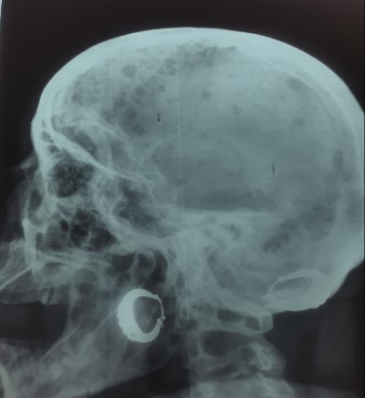

The patient also reported chest pain, which led to a stress echocardiogram before hospitalization, which was then negative. A complete blood count revealed a normochromic, non-regenerative microcytic anemia. Thyroid function tests, electrolytes, and hemostasis assessment were unremarkable. Proteinuria of 2.2 g/L was observed, with preserved renal function, as was hyperglobulinemia of 5.7 g/L, (Figure 4) with no evidence of a monoclonal component on immunotyping, albumin of 36.4 g/L, an ESR of 51 mmHg, and a ferritin level of 299 ng/ml. The 8-hour serum cortisol level was low at 50.5 nmol/L. Standard X-rays of the skull, the cervical, dorsal and lumbar spine, the pelvis and the femurs revealed lytic lesions known as "punch-out geodes," appearing as multiple, well-circumscribed, round, oval lacunae with no peripheral reaction (Figure 5).

Figure 5. X-ray of the skull profile highlighting geodes